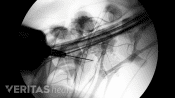

Injections relieve neck and back pain by delivering medications directly to the affected area, reducing inflammation.